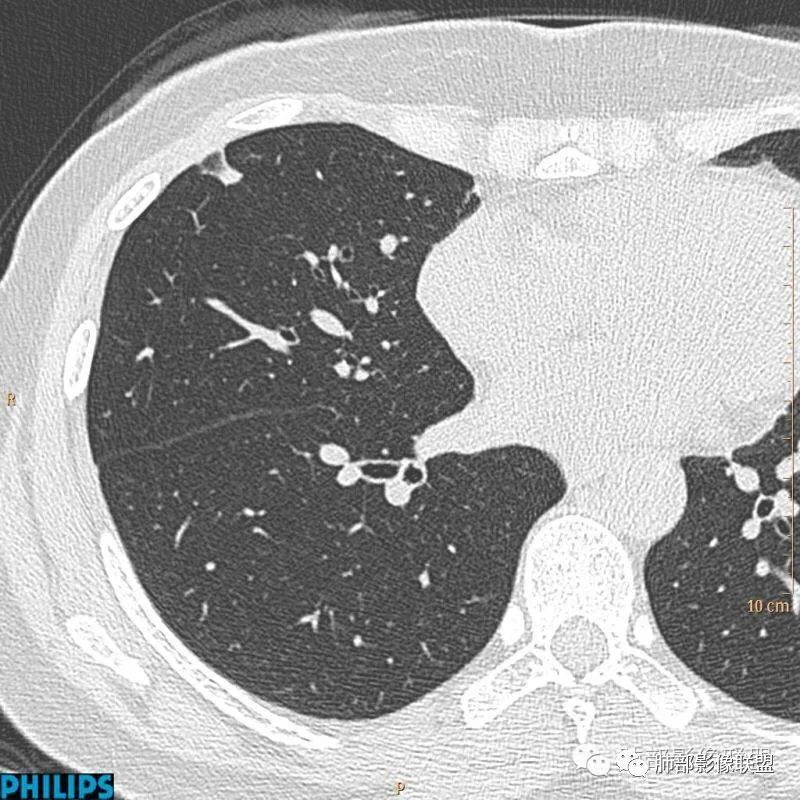

以上病例,有什么共同点?1、病灶均位于胸膜下或叶间胸膜下;

2、病灶边缘多平直,大部分呈三角形,部分呈椭圆形;

3、病灶边缘见一条或数条细线与胸膜相连。

正常情况下,肺内淋巴结是不显示的,一般是慢性炎症所致,老年人和吸烟者多见。影像上常见于胸膜或叶间胸膜下,迄今为止,所有的报道均距胸膜或叶间胸膜小于2.0cm以内。也可以表现为与胸膜或叶间胸膜相贴的结节。绝大多数位于中下叶(气管隆突水平以下),上叶也可见到,但较少见。

长径均小于12mm。典型的形状为三角形,也可以为梭形、圆形或椭圆形。诊断的关键在于见到1-5条细线与胸膜、叶间胸膜或静脉相连,有时状如坐落于电路板的“二极管”,但以薄层CT显示为佳。有作者病理对照线状影为小叶间隔,有作者病理对照为淋巴管。其实不矛盾,因为淋巴管走行于小叶间隔内。

需要与小肺癌、肺转移瘤进行鉴别。肺内淋巴结除细线状影外,边缘清晰无分叶,无毛刺,没有磨玻璃晕,少张力等是与肺癌鉴别的关键。有作者对9例胸膜下的小于1cm的肺转移瘤进行对照,后者均为较为游离的类圆形,无线状影与胸膜或肺静脉相连。

对怀疑肺内淋巴结的病例,必须行薄层扫描,推荐1.5mm及以下层厚。因为在5mm层厚图像,肺内淋巴结可以由于部分容积效应表现为磨玻璃密度结节,而且对线状影及病变形状的显示也欠清晰。

诊断肺内淋巴结最关键指出在于薄层扫描见到细线状影与胸膜、叶间胸膜及肺静脉相连。